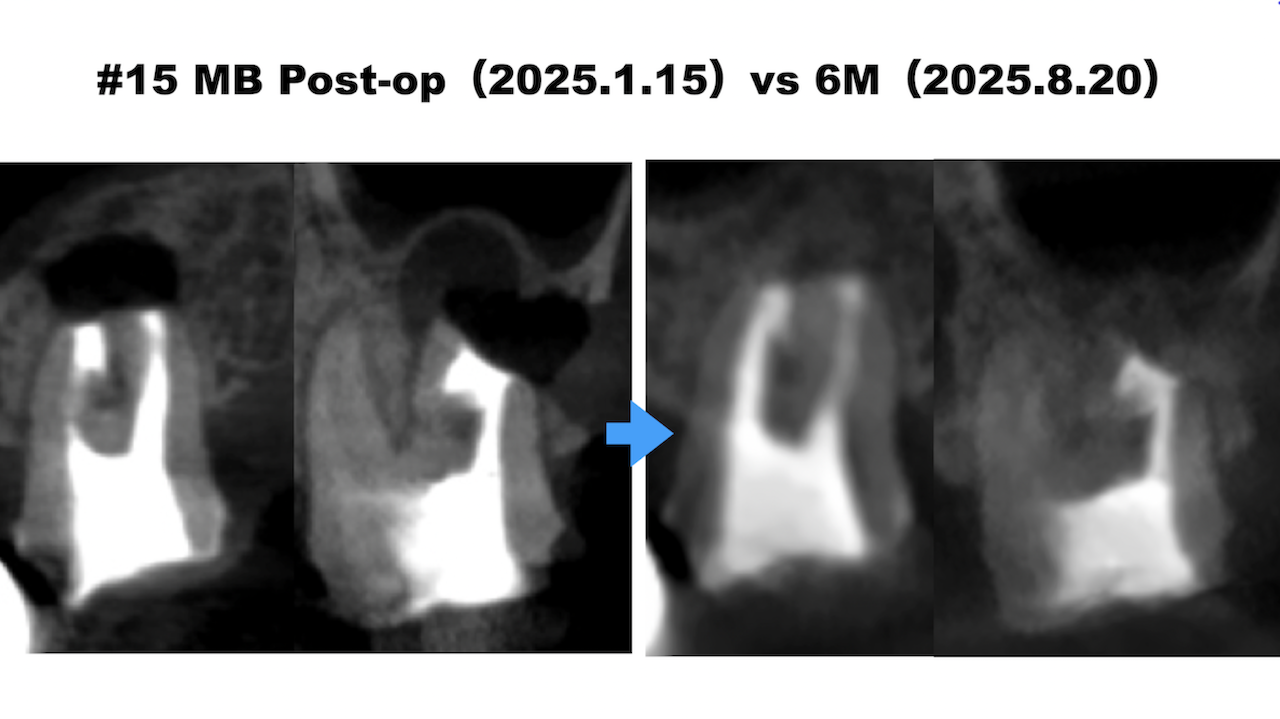

最後にIntentional Replantationが困難な歯に対するApicoectomyについて解説した。